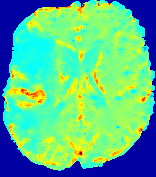

LesionRefer to captionRefer to captionRefer to captionRefer to captionRefer to captionRefer to caption𝐕rgbsubscript𝐕𝑟𝑔𝑏{\bf{V}}_{rgb}Refer to captionRefer to captionRefer to captionRefer to captionRefer to captionRefer to caption𝐕2subscriptnorm𝐕2{\|\bf{V}}\|_{2}Refer to captionRefer to captionRefer to captionRefer to captionRefer to captionRefer to captionRefer to caption3.53.53.52.82.82.82.12.12.11.41.41.40.70.70.70.00.00.0(mm/s)𝑚𝑚𝑠(mm/s)D𝐷DRefer to captionRefer to captionRefer to captionRefer to captionRefer to captionRefer to captionRefer to caption0.0200.0200.0200.0160.0160.0160.0120.0120.0120.0080.0080.0080.0040.0040.0040.0000.0000.000(mm2/s)𝑚superscript𝑚2𝑠(mm^{2}/s)Slice #1Slice #2Slice #3Slice #4Slice #5Slice #6

Figure 4: PIANO feature maps for another patient in the ISLES 2017 training set, where the lesion is located in the right hemisphere. Top row: segmented stroke lesion region (white) on different slices. The corresponding slices for the PIANO feature maps are shown in the following rows.

For a better insight into an estimated velocity field 𝐕𝐕{\bf{V}} and diffusion field 𝐃𝐃{\bf{D}}, we compute the following maps: (1) 𝐕rgbsubscript𝐕𝑟𝑔𝑏{\bf{V}}_{rgb}: Color-coded orientation map of 𝐕=(Vx,Vy,Vz)T𝐕superscriptsuperscript𝑉𝑥superscript𝑉𝑦superscript𝑉𝑧𝑇{\bf{V}}=(V^{x},V^{y},V^{z})^{T}, obtained by normalizing 𝐕𝐕{\bf{V}} to unit length and mapping its 3 components to red, green, blue respectively; (2) 𝐕2subscriptnorm𝐕2\|{\bf{V}}\|_{2}: 222 norm of 𝐕𝐕{\bf{V}}; (3) D𝐷D: scalar field in Eq. 5.

Fig. 3 and Fig. 4 show the PIANO feature maps estimated from two ISLES 2017 patients: all are highly consistent with the lesion in both cases. Details of the blood flow trajectories are revealed in 𝐕rgbsubscript𝐕𝑟𝑔𝑏{\bf{V}}_{rgb} by the ridged patterns and the sharp changes of colors in the unaffected (right) hemisphere, while the flat patterns appearing within the lesion provide little directional information about the velocity and indicate low velocity magnitudes. Velocity magnitudes are more directly visualized via 𝐕2subscriptnorm𝐕2\|{\bf{V}}\|_{2}, from which one can easily locate the lesion where 𝐕2subscriptnorm𝐕2\|{\bf{V}}\|_{2} is low. D𝐷D also indicates lower diffusion values in the lesion, though with less contrast potentially due to the fact that it captures the accumulated effect of CA diffusion at the voxel-level.